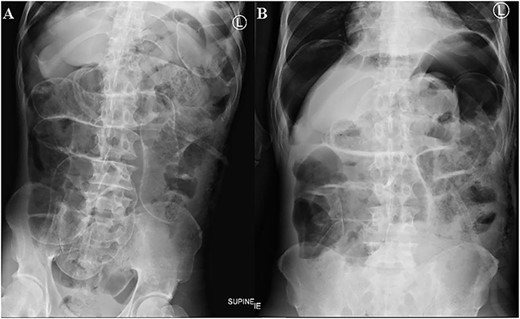

The patient was re-admitted 12-day post discharge complaining of leak per GFT insertion site. There was significant peristomal leakage (Fig. 6). He was in a gasping state with cold extremities. The blood pressure and saturation was unrecordable with a respiratory rate of 28 breaths per minute and a weak pulse rate of 50 beats per minute. The chest had basal crepitations on the right lung. Abdominal X-ray showed features of small bowel obstruction with pneumoperitoneum and right sided pleural effusion was noted (Fig. 7). He was supported with high flow oxygen and resuscitated with IV fluids but 3-h post admission the patient succumbed.

Supine (A) and erect (B) abdomen X-rays show dilated small bowel loops with multiple air fluid levels. Free air seen underneath the hemidiaphragm bilaterally and outlining both sides of the small bowel walls (Rigler sign) suggestive of pneumoperitoneum.